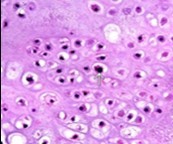

Figure 6.Enchondroma exemplifying lobules of hyaline cartilage composed of enlarged, vacuolated cells with uniform nuclei. Focal calcification is absent 14

Figure 7.Enchondroma enunciating lobular hyaline cartilage with constituent vacuolated chondrocytes an uniform nuclei 15.